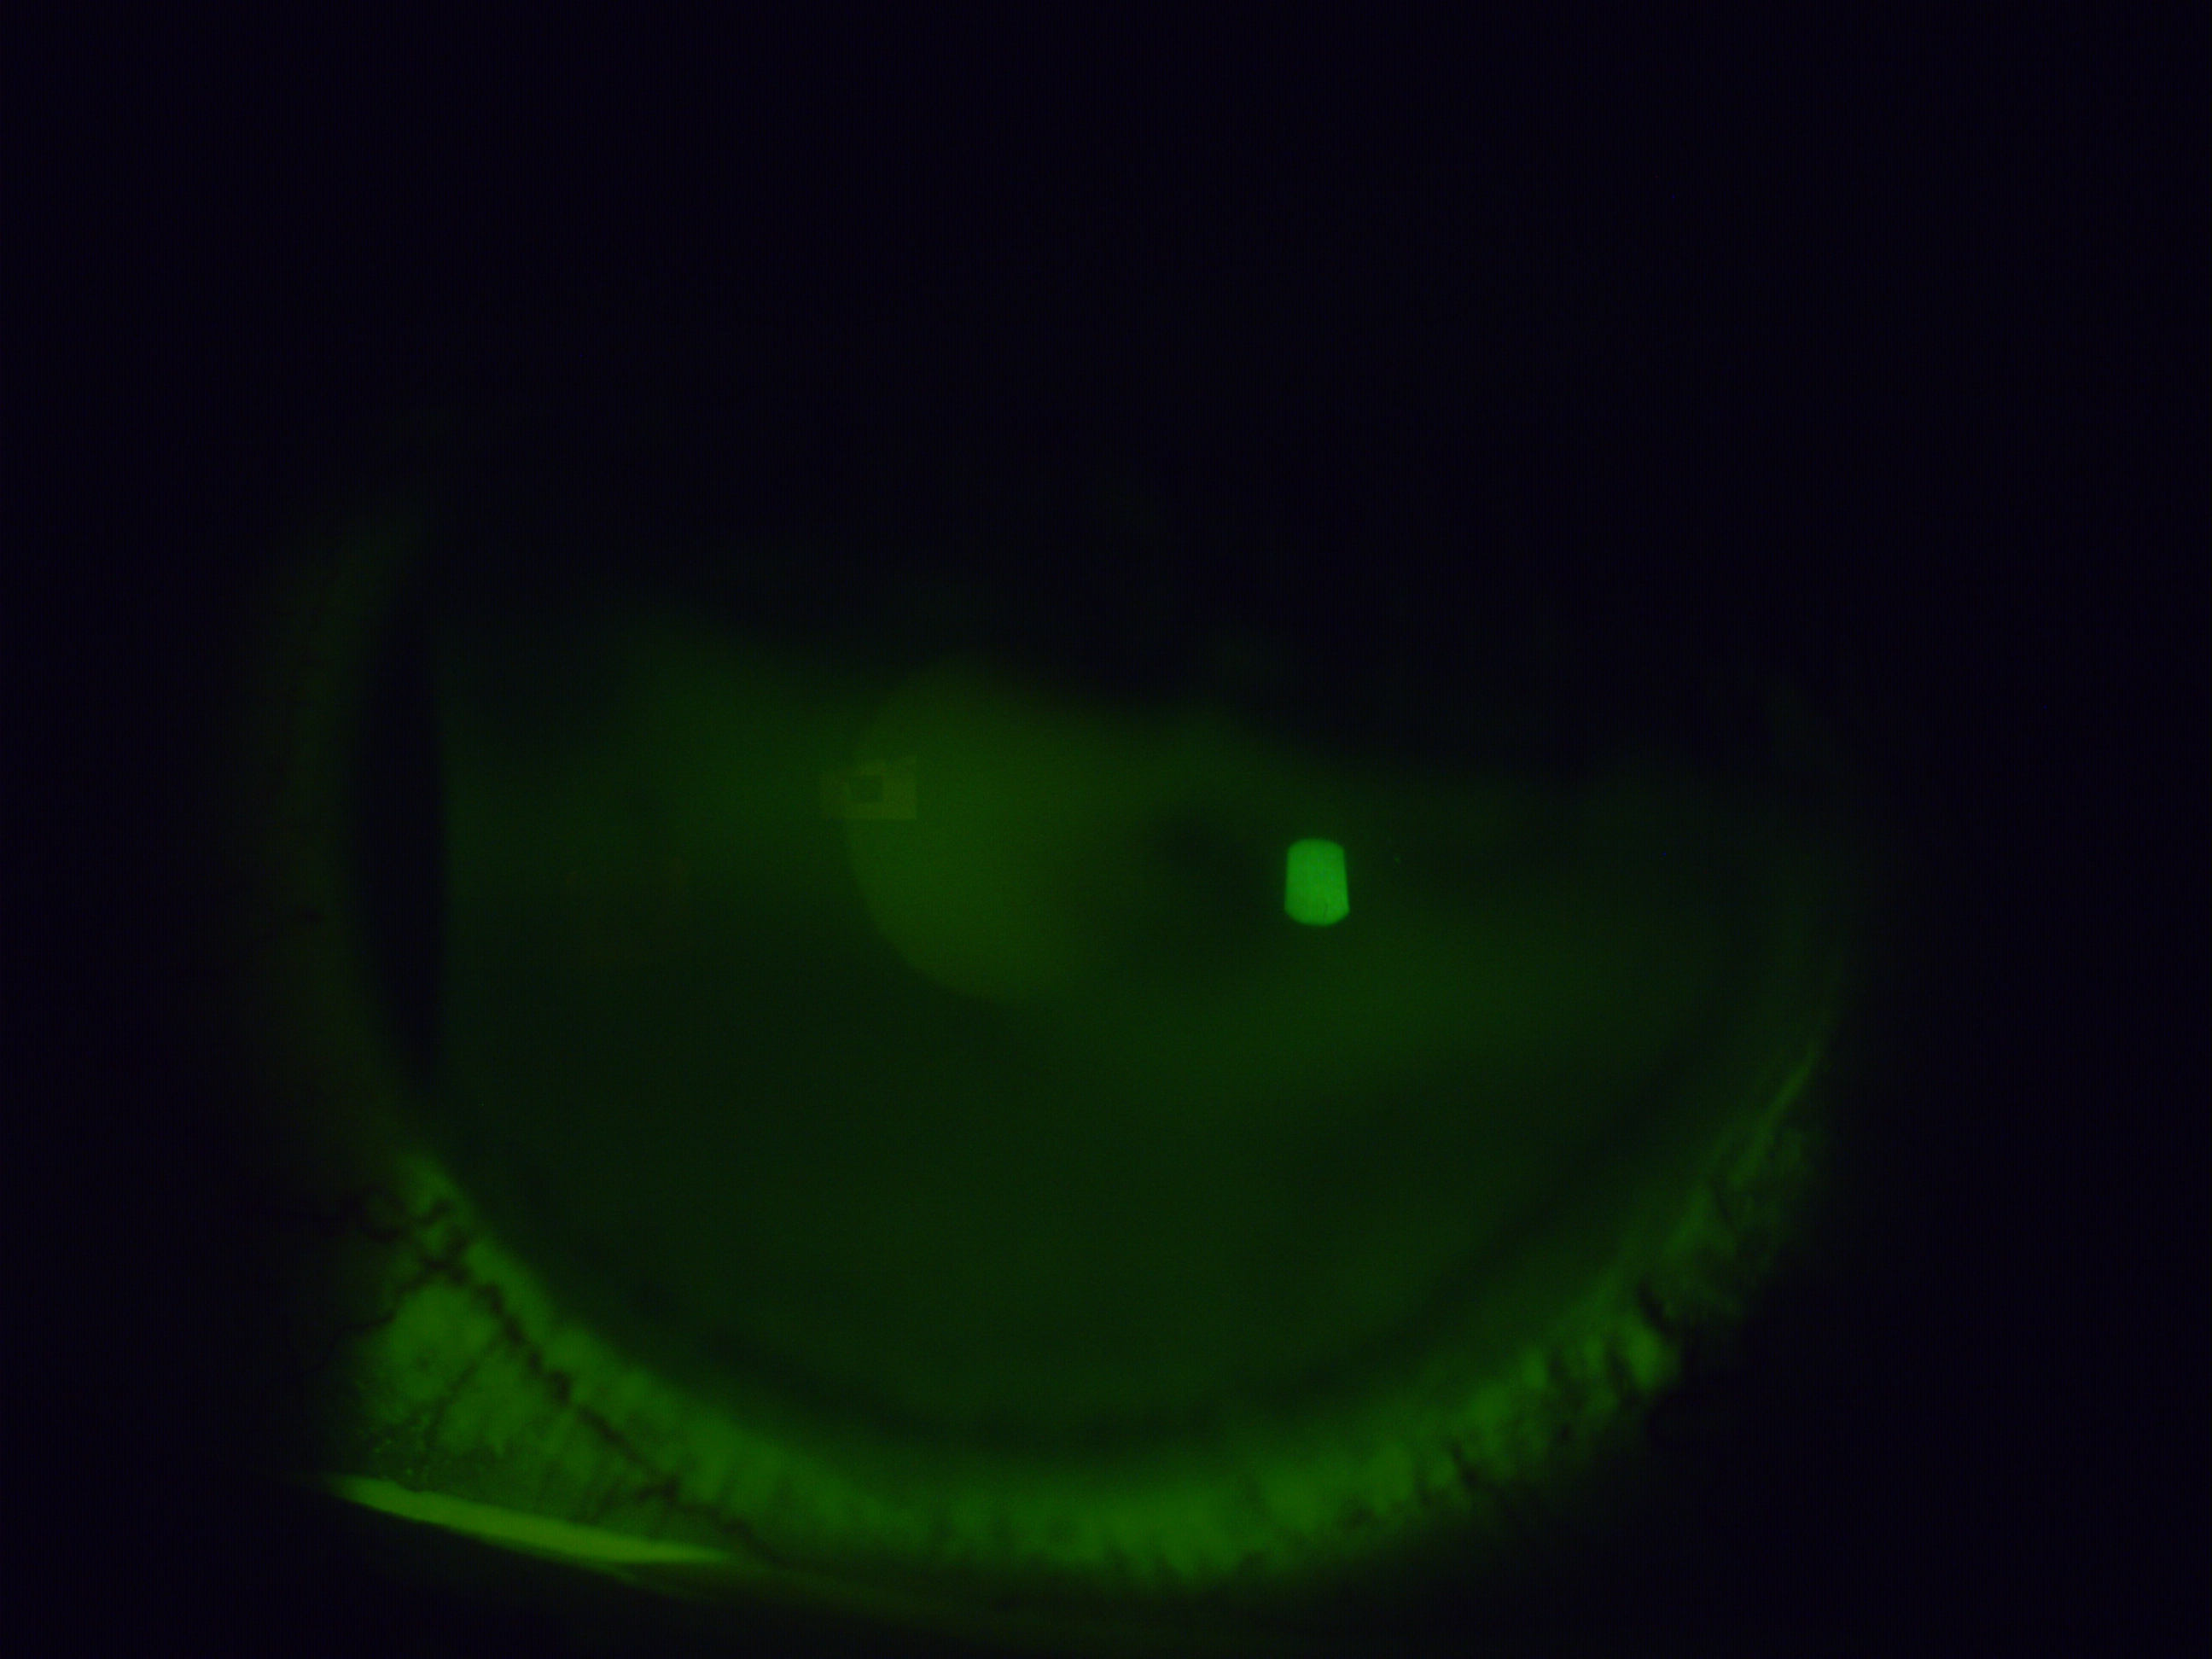

The images below were taken on presentation using fluorescein dye under cobalt blue light — damaged areas of the eye's surface absorb the dye and fluoresce brightly, showing the extent of the problem directly.

The improvement to the surface integrity is visible directly in the fluorescein image taken one week after removal — and reflected in the patient's symptoms. The chronic redness, the surface staining, and the subjective discomfort all showed meaningful improvement, with further gradual recovery continuing in the weeks that followed.